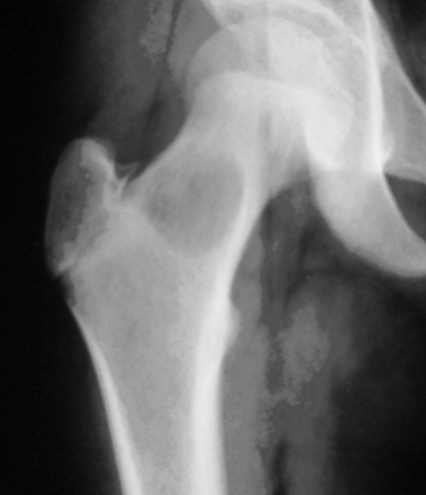

What is seen on radiographs with unicameral bone cysts?